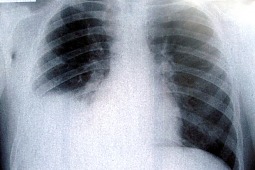

Gruźlica już nie dziesiątkuje ludzkości, jednak nadal stanowi wyzwanie dla lekarzy. Z roku na rok liczba zachorowań rośnie. W 2011 roku w skali kraju odnotowano około 10-proc. wzrost liczby stwierdzonych przypadków. W 2010 roku zarejestrowano 7509 przypadków gruźlicy, w 2011 roku – 8400. Dlatego informacja, że odkryto właściwości pyridomycyny, która niszczy bakterie, ale też zmniejsza ryzyko nabycia przez nie oporności, jest bardzo istotna.